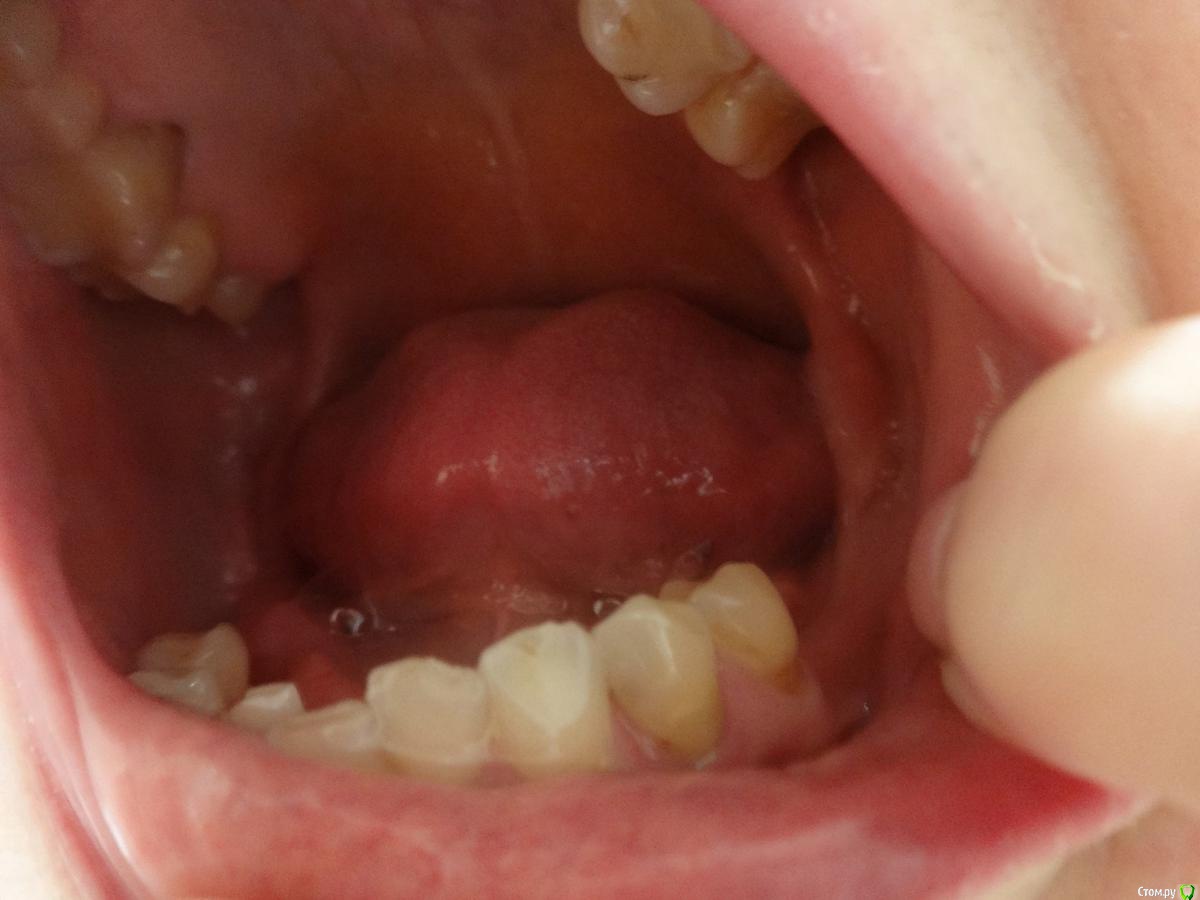

Посоветуйте как мне быть дальше? Пролечила кариес и переделала старые пломбы (снимок до лечения) - даже 8ка нашлась, думала, что все давно поудаляла :).

У меня на верхней челюсти стоит мост из металлокерамики 6 зубов с 13 по 23 делали в 2000 г. Отсутствовали обе единицы. Протезировала несколько раз с 19 лет, была резекция верхушки зуба с кистой сначала одного, потом другого. Затем удалила корни и была попытка наращивания кости гранулами, но прошла неудачно - материал не прижился и от имплантации пришлось отказаться. В итоге, согласилась на мост из МК, но врач настоял на том, чтобы не потерять через некоторое время опорные двойки ставить мост и на клыки. До сих пор жалею, что депульпировала и обточила 4 зуба, чтобы закрыть дыру их двух :(

15 остался корень - сломалась МК коронка на штивте или вкладке (?) - планирую имплантацию одновременную с удалением корня, наверно в данном случае это лучше, чем удалить корень и ждать заживления и только потом ставить имплант.

На нижней челюсти отсутствую жевательные зубы 6,7,8 с обеих сторон и очень давно. Совсем не хочется съемный вариант. Понимаю, что кость атрофировалась в это месте. Есть ли шанс поставить импланты?